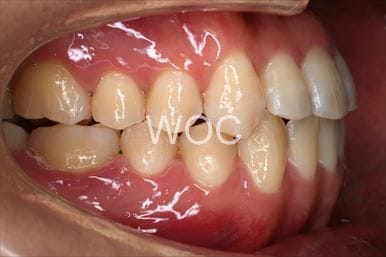

治療後1

治療後2

治療後3

治療後4

治療後5

- 年齢:20歳女性

- 主訴:出っ歯が気になる

- 基本矯正料金:120万円

- 治療期間:1年7ヶ月

- 抜歯部位:上顎両側第一小臼歯